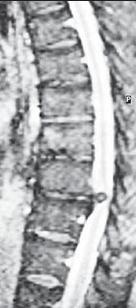

МРТ № 22

МРТ № 23

На МРТ № 22 и МРТ № 23 наблюдаются дорсальные грыжи межпозвонковых дисков в грудном отделе позвоночника